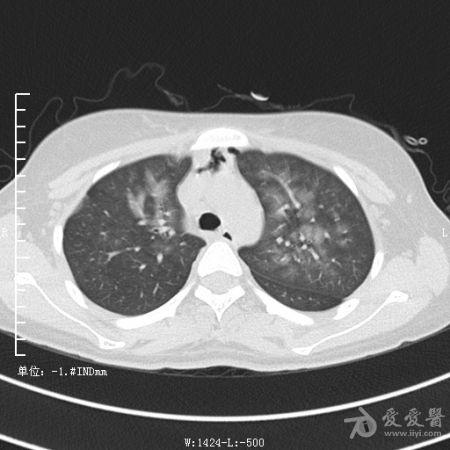

典型支气管扩张及肺水肿CT片

典型支气管扩张肺水肿